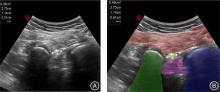

目的 观察内镜手术治疗单侧腰椎间盘突出症的早期临床疗效与坐骨神经横截面积变化之间的关系。 方法 招募2023年6月至2024年6月南昌大学第一附属医院疼痛科52例(n = 52)单侧腰椎间盘突出症患者为研究对象,在手术前以及手术后第4天使用超声测量双侧臀部坐骨结节-股骨大转子水平坐骨神经横截面积值(cross sectional area,CSA),计算坐骨神经横截面积变化△CSA、坐骨神经肿胀率(sciatic nerve swelling rate,SR-SN)。收集患者BMI值(body mass index)、术前、术后第4天视觉模拟量表(Visual Analogue Scale,VAS)、日本骨科协会评分(Japanese Orthopaedic Association Score,JOA)、Oswestry残疾指数(oswestry disability index,ODI)和治疗改善率(treatment improvement rate,TIR)。以评分量表为对照,对坐骨神经横截面积在单侧腰椎间盘突出症中的变化以及其与临床疗效的关系进行分析。 结果 与术前相比,术后第4天VAS、ODI评分降低,JOA 评分升高(P < 0.01),手术后患者临床疗效显著改善。坐骨神经术前患侧CSA值大于健侧(P < 0.01),术后患侧CSA值减小但仍大于健侧(P < 0.01),患侧SR-SN大于健侧(P < 0.01)。患侧△CSA 与术后VAS评分、JOA评分、治疗改善率负相关(P < 0.05);患侧SR-SN与BMI正相关,与术后VAS评分、JOA评分、治疗改善率负相关(P < 0.05);患侧△CSA、SR-SN与ODI评分无明显相关性(P > 0.05)。 结论 在经内镜手术治疗的腰椎间盘突出症患者中,患侧坐骨神经横截面积手术前后的变化越大,术后早期症状改善越明显。

Objective To investigate the correlation between early clinical outcomes following endoscopic surgery for unilateral lumbar disc herniation and variations in the cross?sectional area of the sciatic nerve. Methods Fifty?two patients (n = 52) with unilateral lumbar disc herniation were recruited from June 2023 to June 2024 at the Pain Department of the First Affiliated Hospital of Nanchang University. The cross?sectional area (CSA) values of bilateral sciatic nerves were measured at the gluteal sciatic tuberosity?great femoral rotor level using ultrasound before and on the 4th day after surgery. The change in nerve cross?sectional area ΔCSA and sciatic nerve swelling rate (SR?SN) were calculated. Patient BMI (Body Mass Index), visual analog scale (VAS), Japanese Orthopaedic Association score (JOA), Oswestry Disability Index (ODI), and Treatment Improvement Rate (TIR) were collected preoperatively and on postoperative day 4. Changes in sciatic nerve cross?sectional area in unilateral lumbar disc herniation and its relationship to clinical outcomes were analyzed using the scoring scales as controls. Results Compared to the preoperative period, there was a significant decrease in VAS and ODI scores, as well as an increase in JOA score on the 4th postoperative day (P < 0.01). Furthermore, surgical intervention led to substantial improvement in clinical outcomes for the patients. Prior to surgery, the CSA value of the affected side of the sciatic nerve was greater than that of the healthy side (P < 0.01). Although CSA value decreased on the affected side after surgery, it remained higher than that of the healthy side (P < 0.01). Additionally, there was a significant difference between SR?SN values on both sides with higher values observed on the affected side (P < 0.01). Notably, △CSA on the affected side exhibited a negative correlation with postoperative VAS score, JOA score, and treatment improvement rate (P < 0.05); The SR?SN on the affected side exhibited a positive correlation with BMI and negative correlations with postoperative VAS score, JOA score, and treatment improvement rate (P < 0.05). However, no significant correlations were observed between △CSA, SR?SN, and ODI score on the affected side. (P > 0.05). Conclusions In patients undergoing endoscopic surgery for lumbar disc herniation, a greater change in the cross?sectional area of the affected sciatic nerve before and after the operation is associated with more pronounced improvement in early symptoms. However, further investigation is required to explore the relationship between this change and recovery of both lumbar spine and lower limb function.